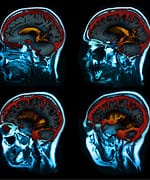

Combating Aging and Brain DiseaseNow that BioMarker scientists have developed a screening model for caloric-restriction mimetics and have identified key genes that are involved in the response to caloric restriction by the heart and liver, they are now looking into caloric restriction’s effects on brain health. Neurodegenerative diseases such as Alzheimer’s and Parkinson’s, as well as age-related cognitive decline, are all major targets of pharmaceutical industry research. Caloric restriction’s neuroprotective effects, as demonstrated in animal models, are profound and likely to be produced in humans as well. Scientists are studying the brain using the same approach used to evaluate caloric restriction-responsive genes in the heart and liver, but with a twist. Rather than subject the entire brain to gene-expression analysis, a new technology allows for examination of specific regions of the brain. The Arcturus Laser Capture Microdissection (LCM) and Laser Cutting System connects a microscope to a UV laser. Thin frozen sections of the brain can be viewed through the microscope, and the system can be programmed to “harvest” cells from specific brain regions. Our studies are focusing on the hippocampus, which is involved in spatial learning and memory, and is one of the first regions of the brain to suffer damage from Alzheimer’s disease. The LCM has been used to collect specific hippocampal neurons for RNA preparation (ribonucleic acid, which is involved in transmitting genetic expression) prior to subjecting the material to gene-expression profile analysis. Figures 1 and 2 show stained hippocampal neurons before and after harvesting with the LCM. BioMarker scientists hope to identify specific brain genes that respond to caloric restriction, and to use this information in developing caloric-restriction mimetics that will ward off disabling neurodegenerative diseases and enable our brains to remain healthy and youthful in advancing age. SummaryWe are living in a time of rapid technological advances. Longevity genes identified in yeast, worms, flies, and mice are directly relevant to humans. The powerful health and longevity benefits of caloric restriction in animals are now being demonstrated in humans. Scientists are actively pursuing intervention strategies based on the caloric-restriction model. The Life Extension Foundation has been a pioneer in funding research and charting the course for one of the most important scientific endeavors of all time: the search to understand how genes determine human life span, and how we can manipulate these genes to live longer, healthier lives. Humans seeking to slow aging and reduce degenerative disease risk may consider reducing food intake and ingesting 20-40 mg of resveratrol and 250-850 mg of metformin each day. These doses are based on studies conducted at BioMarker as well as analysis of the most current scientific literature. Caution: Those suffering from malnutrition should not attempt to restrict their calorie intake. Likewise, people who have medical conditions such as hypoglycemia, or liver or kidney disorders, should not take the prescription drug metformin. Always consult your physician before taking any prescription drug or nutritional supplement. | |||||||